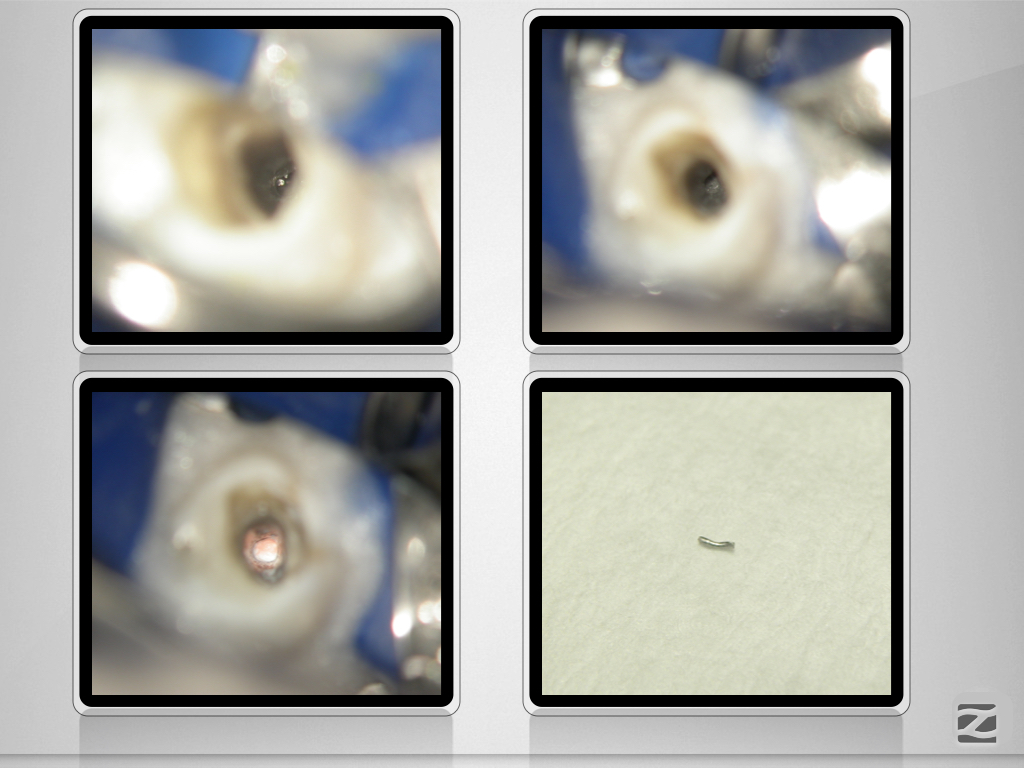

Prämolaren sind (nicht) einfach!